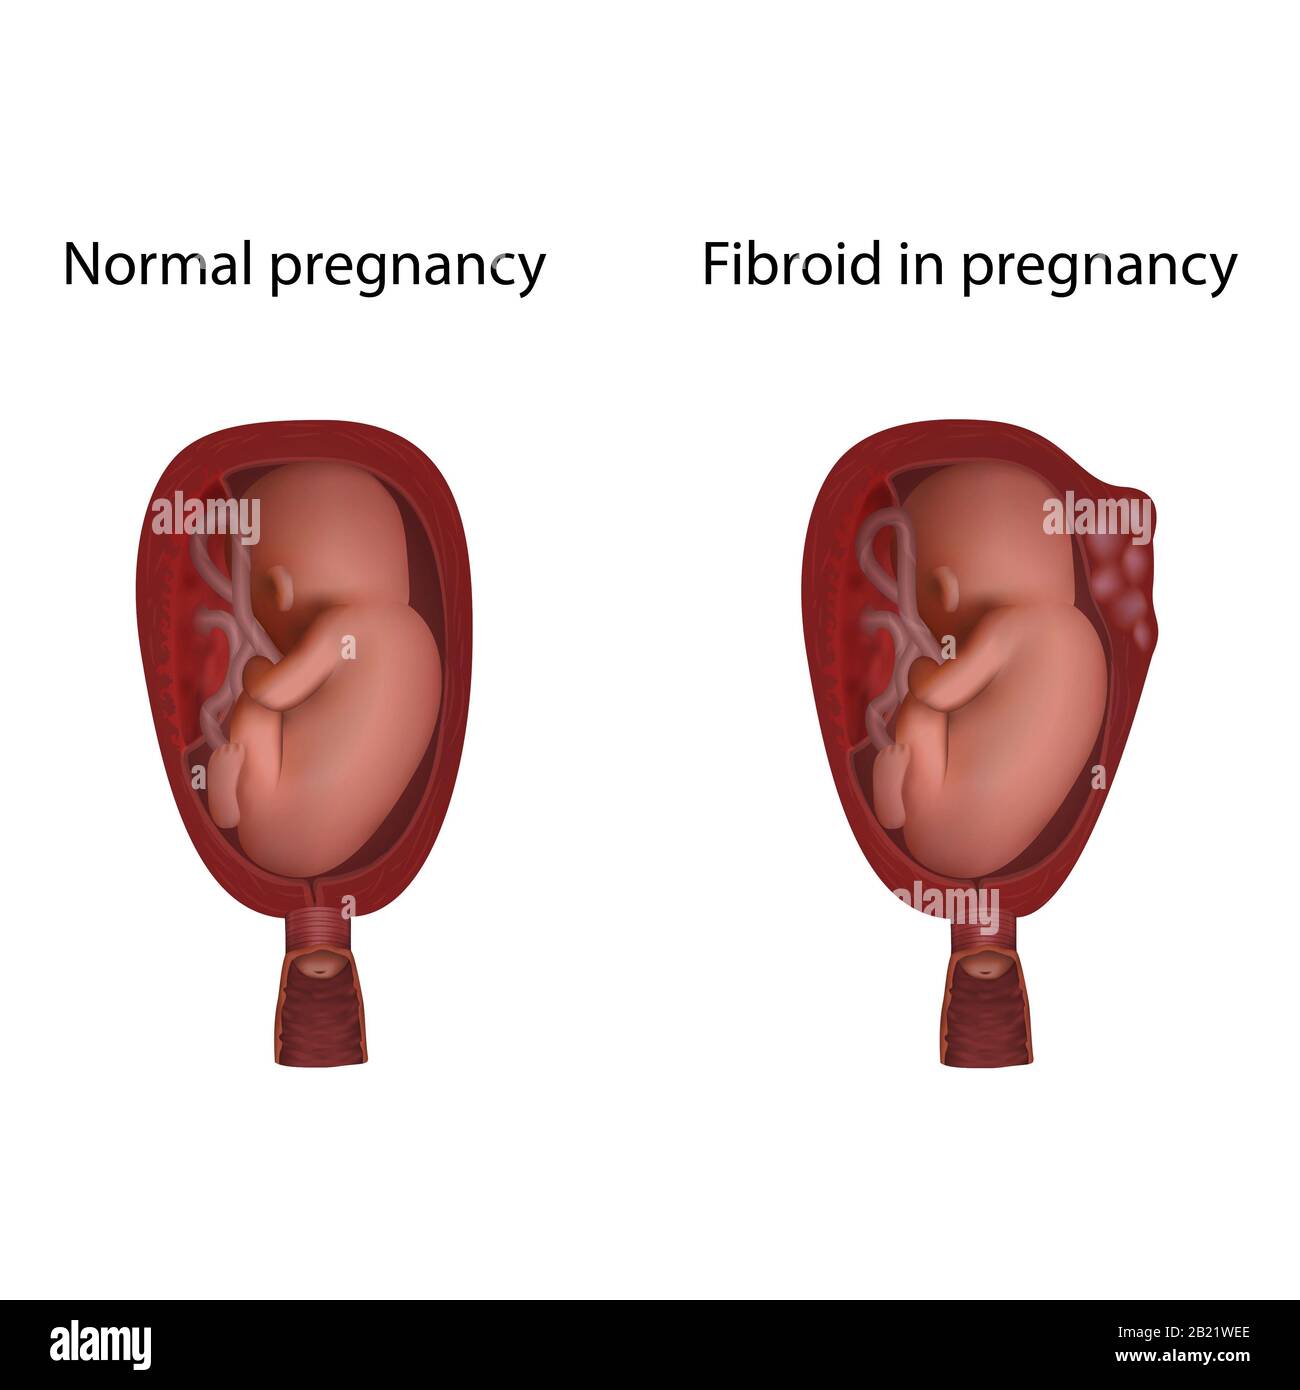

Fibroid in pregnancy and normal pregnancy, illustration Stock Photo – Alamy

Fibroids and Infertility ~ The Surrogacy Doctor- Dr Samit Sekhar

IUP with a fibroid • Sonosession